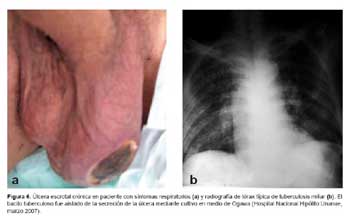

Tuberculosis: diversas manifestaciones de una misma enfermedad

Tradicionalmente se ha definido a la sífilis como la gran simuladora de las enfermedades infectocontagiosas, sin embargo la tuberculosis es igual de proteiforme en cuanto a sus manifestaciones clínicas. Esto se debe, entre otras causas, a tres factores importantes.

El primero, su capacidad de diseminación por vía hematógena y linfática. Esto le confiere la facultad de alterar la morfología y funcionamiento de virtualmente todos los órganos del cuerpo humano, incluso muchos años luego de la primo-infección, debido a su habilidad para permanecer latente en los mismos.

Estas manifestaciones atípicas de tuberculosis, tan variables, deben generar sospecha en el personal de salud, siendo una enfermedad muy prevalente en nuestro medio. Debemos recordar que ante un cuadro clínico raro, es más probable la manifestación atípica de una enfermedad frecuente que la manifestación típica de una enfermedad infrecuente.

Todo médico peruano debe conocer a fondo, no sólo la clásica radiografía de tórax con infiltrado apical o caverna, tan representativas de esta condición, sino también debe estar atento a solicitar las pruebas pertinentes ante posibles cuadros raros de esta enfermedad, que sin ninguna duda en los próximos años seguiremos viendo frecuentemente en los consultorios y salas de nuestros hospitales.